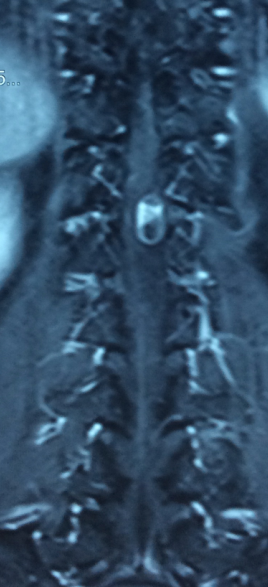

主诉:左下肢麻痛半年,加重伴乏力2周。 病史:患者半年前无明显诱因出现左下肢麻痛,腰部疼痛不明显,久站后有酸胀感。加重伴乏力2周;患者目前无二便失常。患者一般情况尚可。

体查:脊柱无明显畸形侧凸。各棘突及棘旁无明显压痛;左下肢肌力较右侧稍减弱,余四肢肌张力、感觉等无明显异常;双侧膝反射、踝反射无明显异常。病理征未引出。 辅助检查:三大常规、血生化检查未见明显异常,主要脊柱影像学检查如下,请参阅。

诊断:T12-L1椎管内肿物 治疗:患者入院后尽快完善相关检查,请神经外科会诊。经治疗组讨论,拟行“T12-L1椎管内肿物切除+钉棒内固定术”。

讨论:患者椎管内肿物,从影像学表现上看,主要考虑神经鞘瘤,但确诊需依靠手术的病理,同时根据患者的病理情况决定下一步治疗。